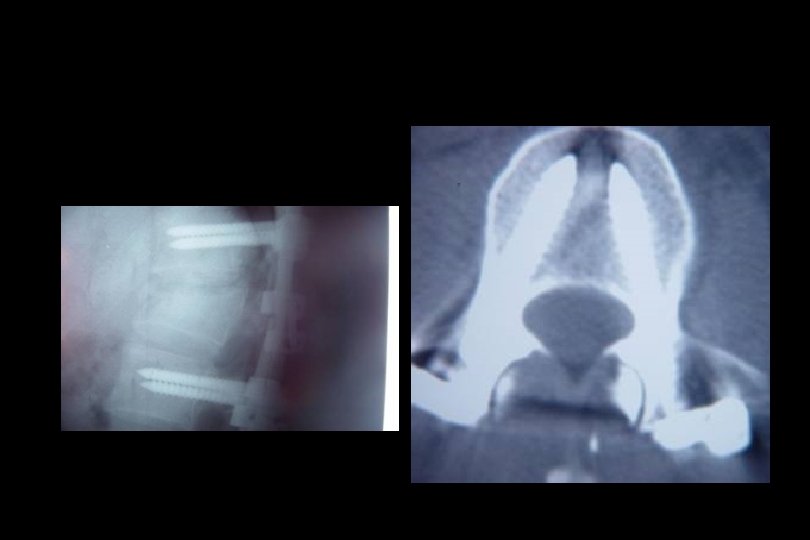

Omurga yaralanmaları • Faset eklem kilitlenmeleri: Genellikle tek yanlı kilitlenmelerde %25’lik, iki yanlı kilitlenmelerde ise %50’den fazla yer değiştirme söz konusudur. AP grafide spinoz çıkıntılar aynı hatta değildir. • T 1 -T 10 kırıkları: Mekanizma genellikle hiperfleksiyondur. Göğüs kafesi nedeniyle bu bölgedeki çökme kırıkları genellikle stabildir. Kifoz 30°den fazla ise ameliyat gereklidir.

Tedavi • İmmobilizasyon • Medikal; Metilprednizolon 30 mg/kg bolus takiben 5. 4 mg/kg/saat 23 saat süre ile Ancak! Yaralanmadan sonraki ilk 8 saat içinde başlanması koşul! GM-1 ganglioside (100 mg/gün)